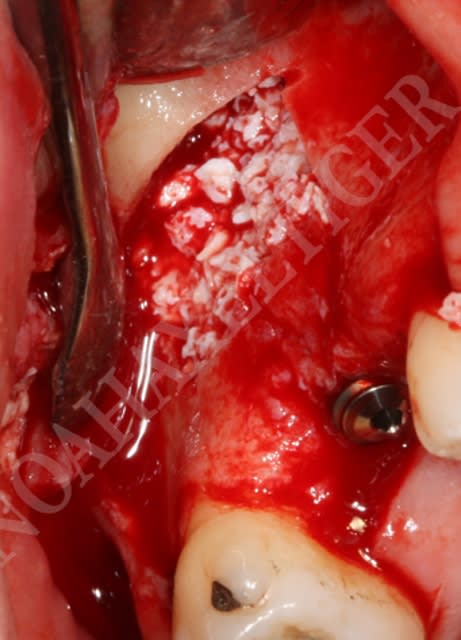

cas clinique avec abord transantral:

Le protocole est le même que lors d’un sinuslift avec pour seule différence la taille plus importante du volet d’accès osseux. L’utilisation du piezo permet une découpe sure et une conservation du volet osseux qui pourra en fin de chirurgie être replacé.

L’élevation de la membrane sinusienne est pratiquée en profondeur jusqu’à atteindre la proéminence de la racine palatine. La suite de l’intervention est pratiquée sous microscope opératoire : la mince couche osseuse recouvrant l’apex palatin est retirée avec un ciseau à os. La racine est réséquée au niveau désiré, l'extrémité de la racine est préparée avec un rétrotip ultrasonique selon les principes de la chirurgie endodontique apicale. L’obturation à rétro se fait avec du MTA.

Une technique appropriée, une manipulation soigneuse du tissu et le recours à des antibiotiques recommandés permettent de réduire au minimum les complications.

Pour faciliter le décollement de la membrane sinusienne j'utilise dans ces cas la technique du ballon avec un simple catether urinaire. Je suture également apicalement la membrane à la paroi latérale sinusienne (2 petits trous dans la paroi osseuse suffisent / même technique que quand on doit réparer une large déchirure de la membrane sinusienne) de facon à éviter que la membrane ne vascille pendant la chirurgie apicale.

Ensuite, miroir endo, microscope et éclairage.

Il est clair aussi qu'il m'est arrivé parfois de ne pouvoir obturer à rétro pour des raisons d'accés. Un compromis certainement à long terme, j'en suis conscient mais l'alternative pour le patient est dans ce cas l'extraction de la molaire.